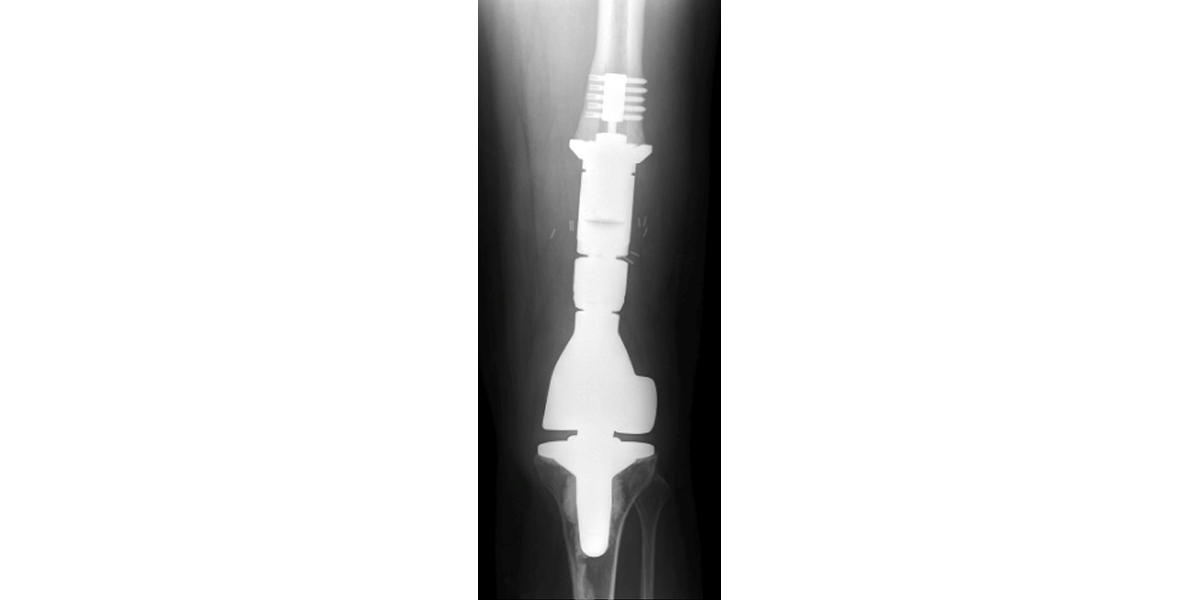

Part of the UCSF’s Orthopaedic Oncology Service, the international Center for Osseointegration Research, Education and Surgery (iCORES) program focuses on basic, clinical, and translational research involving bone-anchored implants. Historically involved in the utilization of the Compress® device for fixation of endoprostheses used in the reconstruction of massive skeletal defects in cancer patients, we are now investigating osseointegration technology to help in the rehabilitation of patients with amputation.  Advanced studies include efforts to develop brain-machine interface systems that enable bidirectional intuitive volitional control of, and sensory/proprioceptive feedback from, external prostheses. Richard J. O’Donnell, M.D. serves as Director of the iCORES program.  He is assisted by Drs. Rosanna L. Wustrack and Melissa N. Zimel.

17. 10-02939 Reconstruction of massive defects using the ComPreSs device for endoprosthetic fixation in the proximal femur, distal femur, proximal tibia and humerus

7. O’Donnell, R.J.: Compressive osseointegration of tibial implants in primary cancer reconstruction. Clin. Orthop. Rel. Res., 467:2807-2812, 2009. doi: 10.1007/s11999-009-0986-4. Epub 2009 Aug 4. PubMed PMID: 19653050.

10. O’Donnell, R.J.: Compressive osseointegration of modular endoprostheses. Current Opinion Orthop., 18:590-603, 2007. doi: 10.1097/BCO.0b013e3282f0dafc.